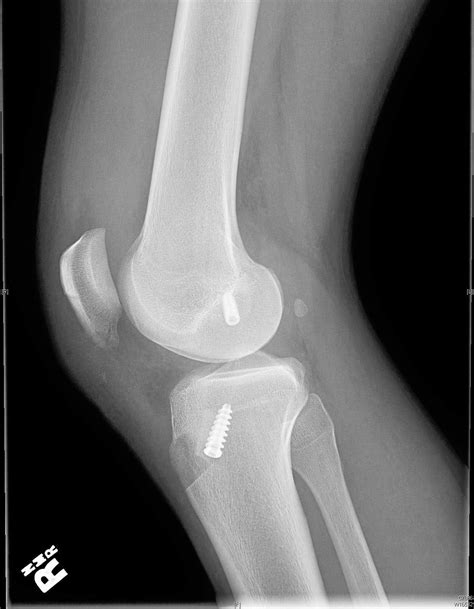

Arthroscopic ACL Reconstruction With Bone Patellar Bone Graft Using

acl reconstruction graft rays xrays discussion patellar